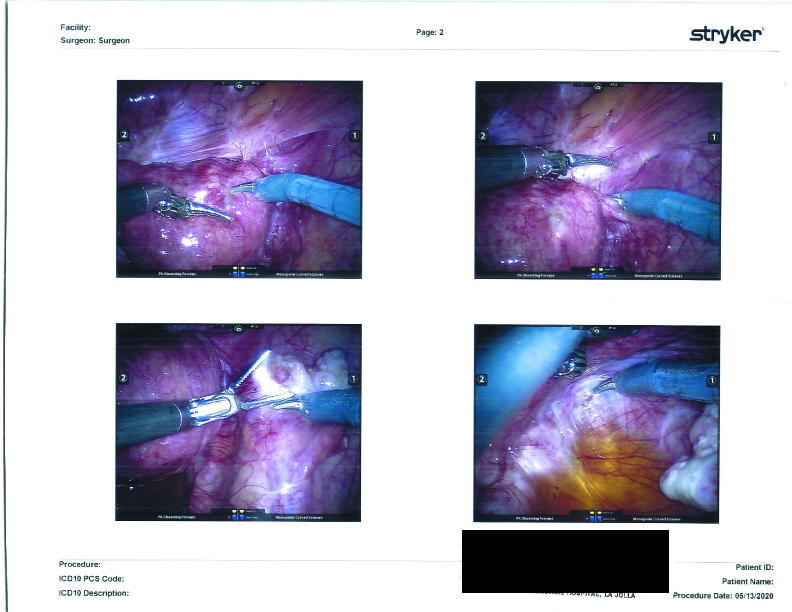

My bladder was stuck to my uterus and pinned there by adhesions. In the photo, it looks very spider-webby.

Endometriosis lesions were found on the outside of my bladder, as well as the right round ligament, the cul-de-sac (also called the Pouch of Douglas), the left round ligament, the left paracolic gutter, and on the sigmoid colon. All of the lesions (except for the sigmoid colon) were excised and packaged up for pathology.

Due to the closeness of the left ureter to the endometriosis lesions near my left ovarian fossa (the little cavity of the pelvis where an ovary sits) and the stuck left ovary against the pelvic wall, my surgeon took great care to keep the left ureter safe from any surgical damage. The left ovary and its cyst were completely removed. We had previously agreed to remove my left ovary due to ongoing pain and it proving to be a problem-child (for lack of a better term) discovered during previous surgeries.

Surgical Photographs

As promised here are the surgery photographs! Please be aware that the scans are low quality; the Endo on the colon is MUCH more visible, almost a dark purple blotch on the hard printouts. If I get higher-quality scans, I’ll be sure to update these. You can click on them for a larger image.